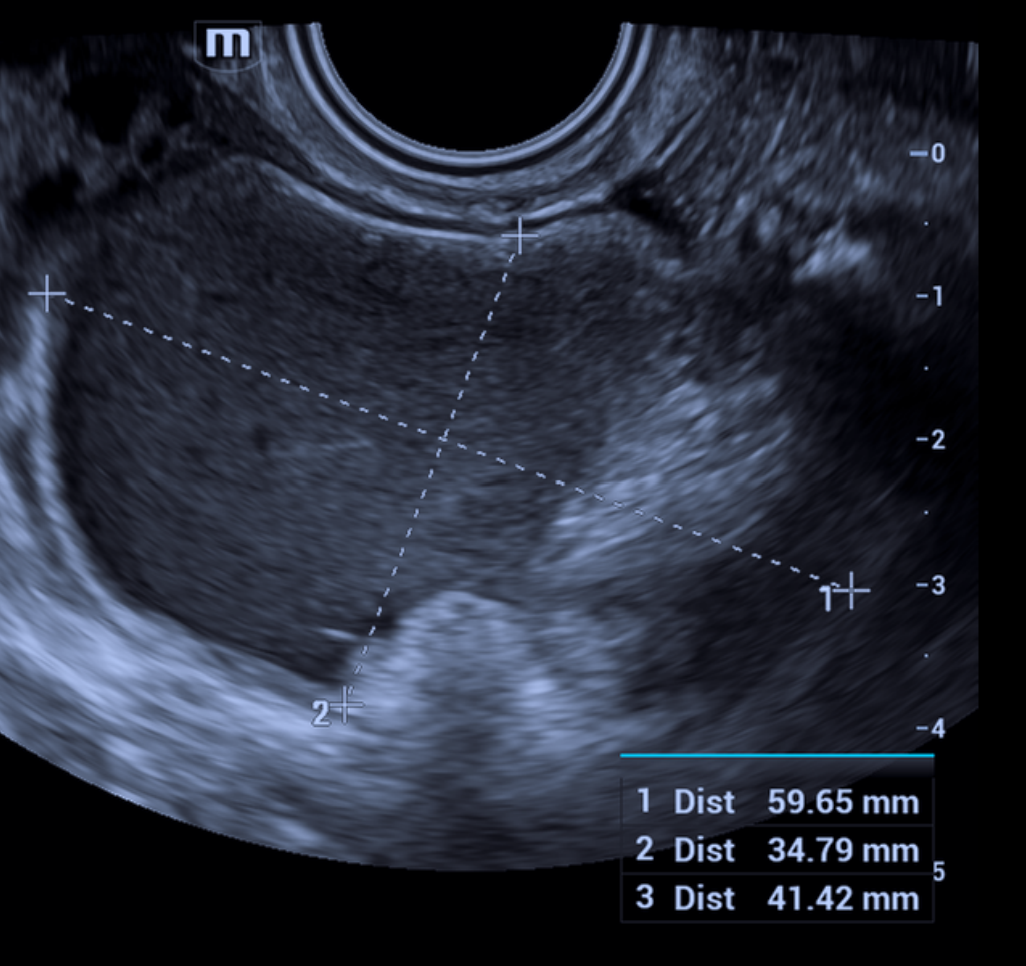

Risco: <10%Cisto unilocular ≥ 10 cm, cistos dermoides/endometriomas/hemorrágicos ≥ 10 cm, cisto unilocular com parede irregular < 3 mm, cisto multilocular < 10 cm com parede lisa, lesão sólida com superfície lisa.

O-RADS US 4 — Risco Intermediário

Risco: 10-<50%Cisto multilocular sem componente sólido ≥ 10 cm ou com IC = 4, cisto unilocular/multilocular com componente sólido, lesão sólida com superfície lisa e IC = 2–3.

Risco: ≥50%Cisto unilocular com ≥ 4 projeções papilares, cisto multilocular com componente sólido e IC = 3–4, lesão sólida com IC = 4 ou superfície irregular, presença de ascite e/ou nódulos peritoneais.